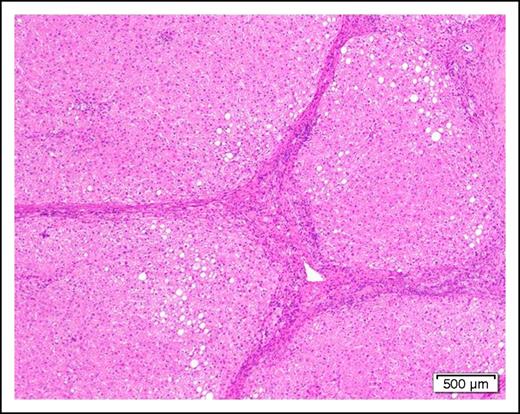

Scenario 6: patient with cirrhosis

A 58-year-old man with cirrhosis (Figure 2) of the liver attributable to chronic alcohol abuse is found to have AML with the mixed-lineage leukemia translocation t(4;11)(q21;q23). He has evidence of portal hypertension as manifested by mild ascites and edema of the lower extremities. The serum albumin is mildly low at 3.0 g/dL and the prothrombin time and partial thromboplastin time are slightly prolonged.

Photomicrograph of a cirrhotic liver illustrating well developed fibrous septa separating irregular regenerative nodules. The hepatocytes show mild steatosis (hematoxylin and eosin stain, original magnification ×40).